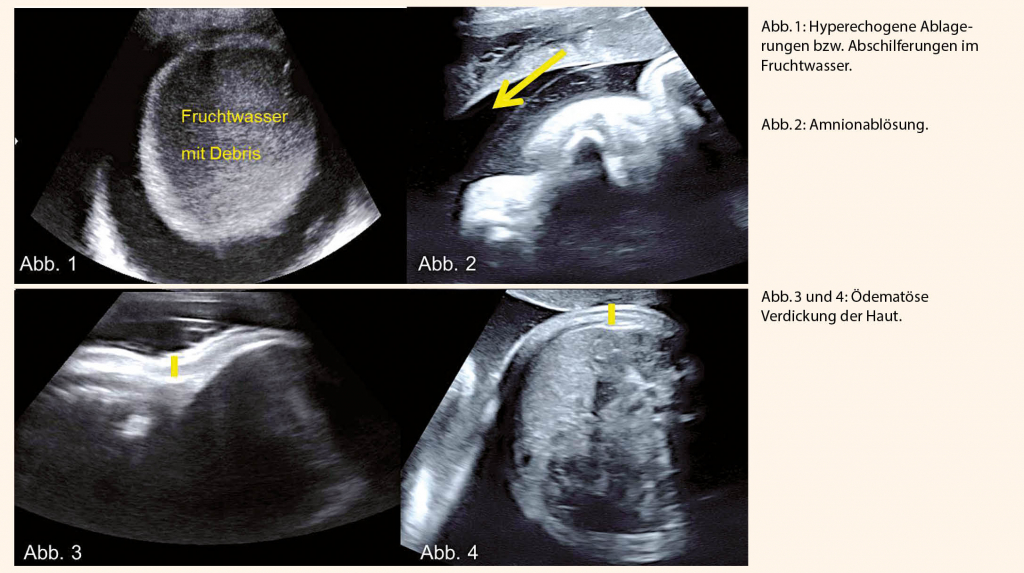

Eine 41-jährige Gravida V, Para II stellte sich das erste Mal bei uns in 37+6 SSW in unserer Gebärabteilung mit regelmässigen Kontraktionen vor. Die ersten beiden Geburten waren unkomplizierte Spontangeburten mit gesunden Kindern. Familienanamnese bland. Der bisherige Schwangerschaftsverlauf gestaltete sich problemlos mit niedrigem Risiko für T21, T18/T13 im ETT sowie unauffälliger, externer Zweittrimestersonographie. Beim Aufnahme-Ultraschall in der Gebärabteilung fielen mehrere Auffälligkeiten auf. Es konnte ein Polyhydramnion mit einem «maximal vertical pocket» von 9 cm dargestellt werden («amnion fluid index» von 22 cm). Innerhalb des Fruchtwassers zeigten sich sehr hyperechogene Ablagerungen bzw. Abschilferungen (Abb. 1). Das Amnion schien vom Chorion im Sinne einer Amnionablösung separiert zu sein (Abb. 2). Die fetale Haut war ödematös und deutlich verdickt (Abb. 3 und 4). Aufgrund der regelmässigen Kontraktionen wurde keine 3D-Sonographie durchgeführt und die Geburt angestrebt.

Sonographische Zeichen einer Ichthyose im Sinne von hyperechogenen Ablagerungen im Fruchtwasser wurden bereits früh beschrieben (6). Zusätzliche Informationen hinsichtlich der Körperoberfläche und der Auffälligkeiten der Extremitäten liefert die 3D- und 4D-Sonographie (7, 8).

- Sonographische Zeichen für den Formenkreis der Ichthyose umfassen hyperechogene Abschilferungen im Fruchtwasser, ödematöse Haut, Fehlstellungen der Extremitäten sowie Auffälligkeiten der Hautober-

fläche, insbesondere des Gesichts, im 3D- bzw. 4D-Ultraschall.